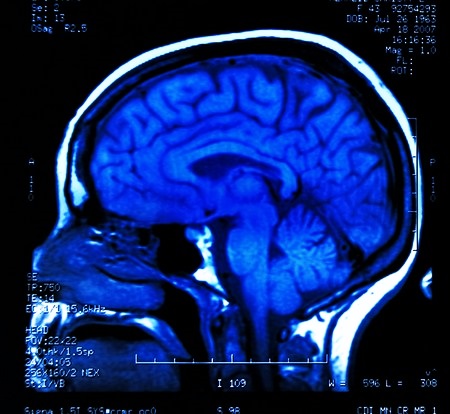

- Затем больному необходимо пройти рентгенографию и получить снимок черепа. Более предпочтительным решением в этом случае является проведение КТ или МРТ, потому что с помощью этих исследований можно будет получить данные не только о костных мозговых структурах, но и о мозговой ткани, сосудах. Эти процедуры необходимы для определения первопричины повышения давления внутри черепа.